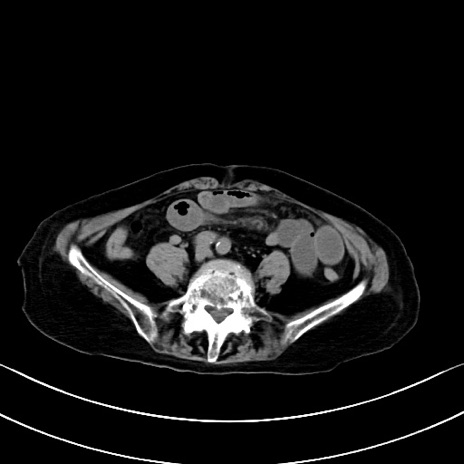

【症例】90歳代女性

【主訴】腹痛・嘔吐

【現病歴】 食欲低下、嘔吐があり昨日他院受診。肺炎と診断され入院となる。入院後より腹部全体に圧痛あり。胃管留置され経過みていたが、症状持続するため、

当院転院となる。

【身体所見】腹部:中央に激痛あり、圧痛あり、反跳痛不明

【データ】WBC 17100、CRP 18.82